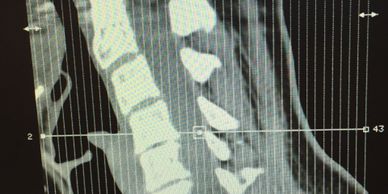

This is a side-view image of how my neck (cervical spine) now looks after dozens of years of impact traumas. The natural "C" shaped curve that my cervical spine used to have is now gone. Without a curve to act as a shock absorber, my 'flat spine' contributes to a long list of pain and tension symptoms all over my body.

My pain was a result of falling off a horse as a child and several hard falls as an adult. The falls contributed to herniated disks in my lumbar spine. Further pain was caused by a car accident that left me on short-term disability for months with accompanying nerve damage and shoulder pain that affect me to this day. But all of my pain